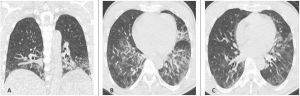

In TCAR si caratterizza per la presenza di aree a “vetro smerigliato” diffuse in entrambi i polmoni come la maggior parte delle polmoniti virali descritte di seguito, queste aree tuttavia si contraddistinguono per la prevalente distribuzione subpleurica e per la presenza nel contesto di ispessimento liscio dei setti interlobulari (Figura 1). Versamento pleurico e linfadenopatie sono reperti più rari.

Figura 1: Uomo di 75 anni con infezione da SARS-CoV-2. Le immagini TC assiali (A-B-C-D) e ricostruzioni MPR sul piano sagittale (E) e coronale (F) mostrano la tipica presentazione della polmonite da COVID-19 caratterizzata dalla presenza di aree di aumentata densità con aspetto a “vetro smerigliato” cui si associa ispessimento liscio dei setti interlobulari che mostrano prevalente distribuzione subpleurica. La localizzazione delle aree di iperdensità in sede subpleurica è caratteristica di questa infezione come evidenziato particolarmente nell’immagine A in cui le aree a “vetro smerigliato” si dispongono lungo la scissura del lobo accessorio dell’azygos e nell’immagine E in cui è evidente la distribuzione delle alterazioni lungo le scissure.